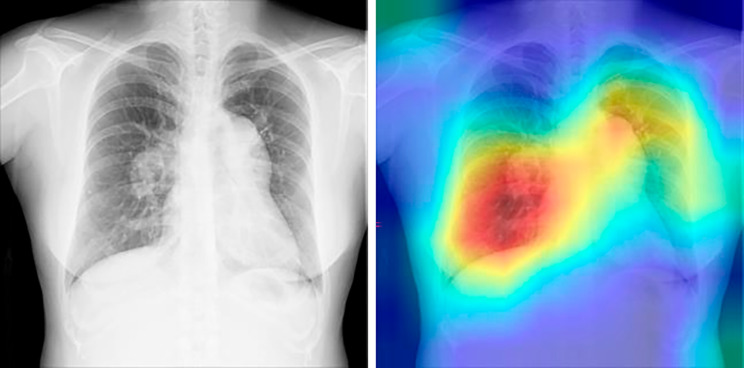

In this study, we developed an algorithm to extract suspected patients with PAH using CXR images and achieved an AUC of 0.988, albeit in a limited population. In a previous study, Kusunose et al. developed an algorithm to predict increased pulmonary arterial pressure using CXR images in a population with suspected PH, obtaining an AUC of 0.71 and a specificity of 0.95 [14]. However, the CAD task used was more difficult than that used in our study because the people in the control group (non-PH) had subjective symptoms and were suspected of having PH. To visualize the focus pixels of the model inference, we used Gradient-weighted Class Activation Mapping (Grad-CAM). This technique specifically allows for the visualization of the focus pixels per image. Figure 3 is a single example to demonstrate the function of the model. Our AI model focused on the pericardial areas of the CXR images (Fig. 3) and appeared to label for the presence or absence of PAH. Nine doctors diagnosed PAH on CXR images by mainly focusing on the enlargement of the pulmonary artery and the heart. The focused area of the AI model and the doctors suggests that the AI model has similar diagnostic criteria to those of the doctors. In cases of false-positive results in the control group, heart enlargement could be considered PAH by the AI algorithm (Supplementary Fig. 1). Whereas in the study by Kusunose et al., the AI program focused on the right upper lung area and the area around the heart because the right upper pulmonary field is generally a common site of focal congestion [14].

Fig. 3.

Analysis of the images where AI was focused. A single example demonstrating the function of the model. This CXR image was taken from a 39-year-old woman, with a mean pulmonary arterial pressure of 62 mmHg and WHO functional class III. Our AI model focused on the pericardial areas of the CXR images. AI: artificial intelligence; CXR: chest X-ray; WHO: World Health Organization